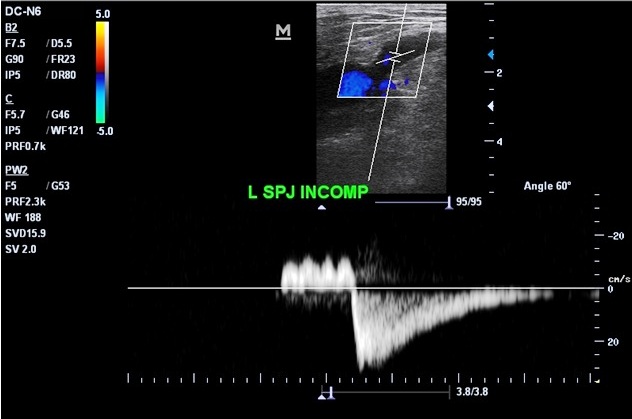

One of the commonest reasons for this examination is to detect venous thrombosis which means clotting of blood in the veins. Varicose veins, which result from incompetence of valves in the veins, is another common reason for doing venous doppler examination. Recurrence of varicose veins or signs of venous incompetence after previous treatment of varicose veins is another important reason for this study.